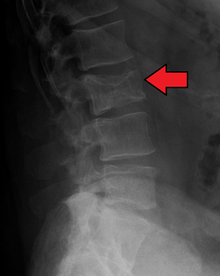

Bone pain affects almost 70% of patients and is the most common symptom.[11] Myeloma bone pain usually involves the spine and ribs, and worsens with activity. Persistent localized pain may indicate a pathological bone fracture. Involvement of the vertebrae may lead to spinal cord compression or kyphosis. Myeloma bone disease is due to the overexpression of receptor activator for nuclear factor κ B ligand (RANKL) by bone marrow stroma. RANKL activates osteoclasts, which resorb bone. The resultant bone lesions are lytic (cause breakdown) in nature and are best seen in plain radiographs, which may show "punched-out" resorptive lesions (including the "raindrop" appearance of the skull on radiography). The breakdown of bone also leads to release of calcium into the blood, leading to hypercalcemia and its associated symptoms.

The work-up of suspected multiple myeloma includes a skeletal survey. This is a series of X-rays of the skull, axial skeleton and proximal long bones. Myeloma activity sometimes appear as "lytic lesions" (with local disappearance of normal bone due to resorption), and on the skull X-ray as "punched-out lesions" (pepper pot skull). Magnetic resonance imaging (MRI) is more sensitive than simple X-ray in the detection of lytic lesions, and may supersede skeletal survey, especially when vertebral disease is suspected. Occasionally a CT scan is performed to measure the size of soft tissue plasmacytomas. Bone scans are typically not of any additional value in the workup of myeloma patients (no new bone formation; lytic lesions not well visualized on bone scan).